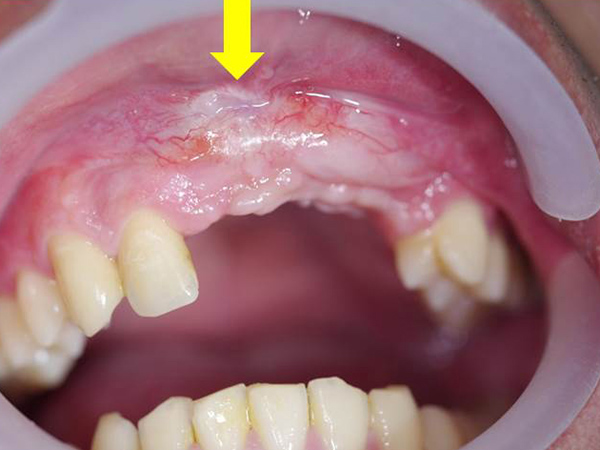

顯微鏡下進行牙周病治療,使用高倍數醫療顯微鏡,360度檢查每顆牙齒牙周狀況,紅色箭頭處可見造成牙周病主因的牙齦下牙結石,使用特殊顯微超音波工具清除後,可見乾淨的牙根表面,幾無出血(黃色箭頭處)。